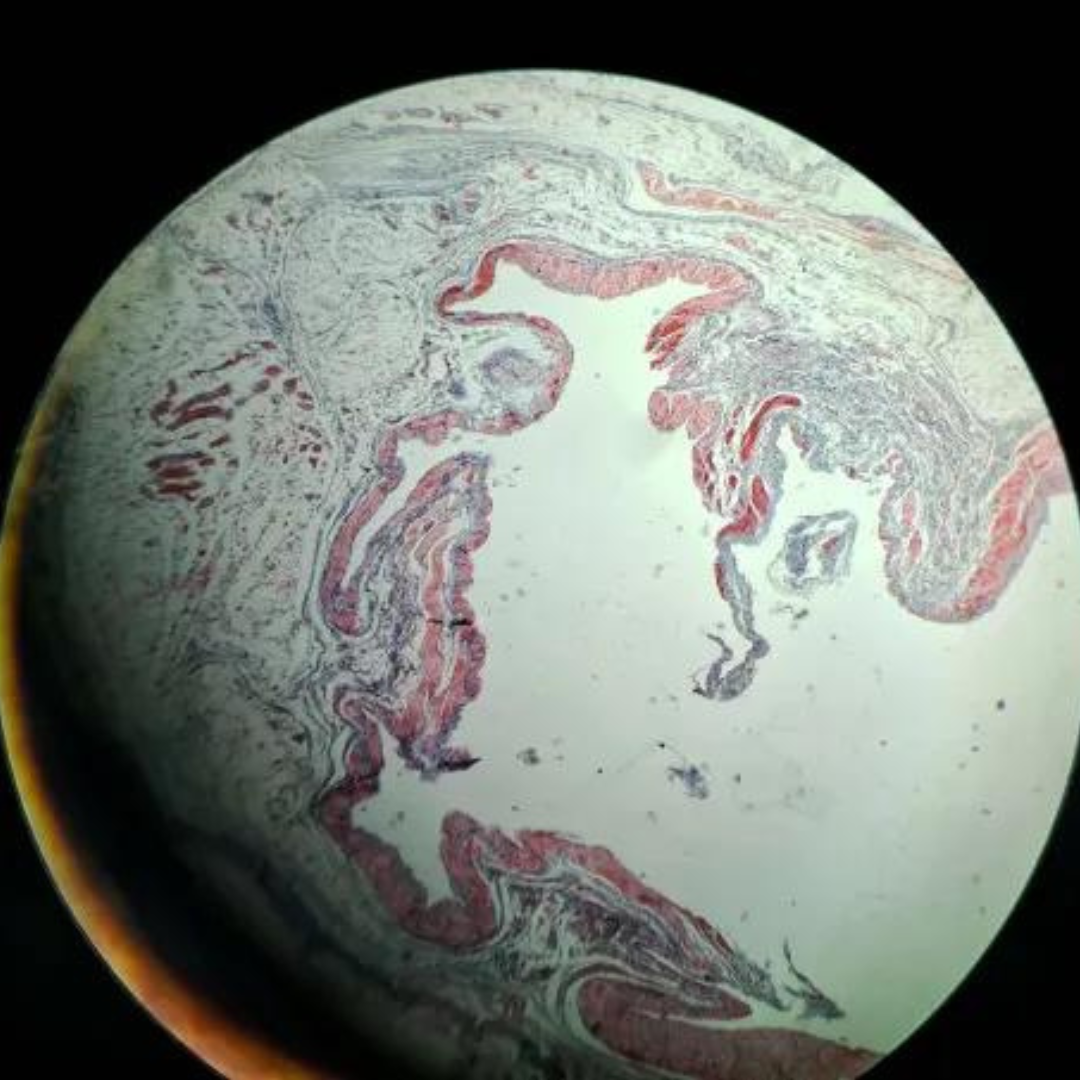

Elastic Arteries (Aorta)

Elastic Arteries (Aorta)

Elastic Arteries (Aorta)